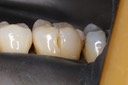

Gary Umeda #12-13 casting try in